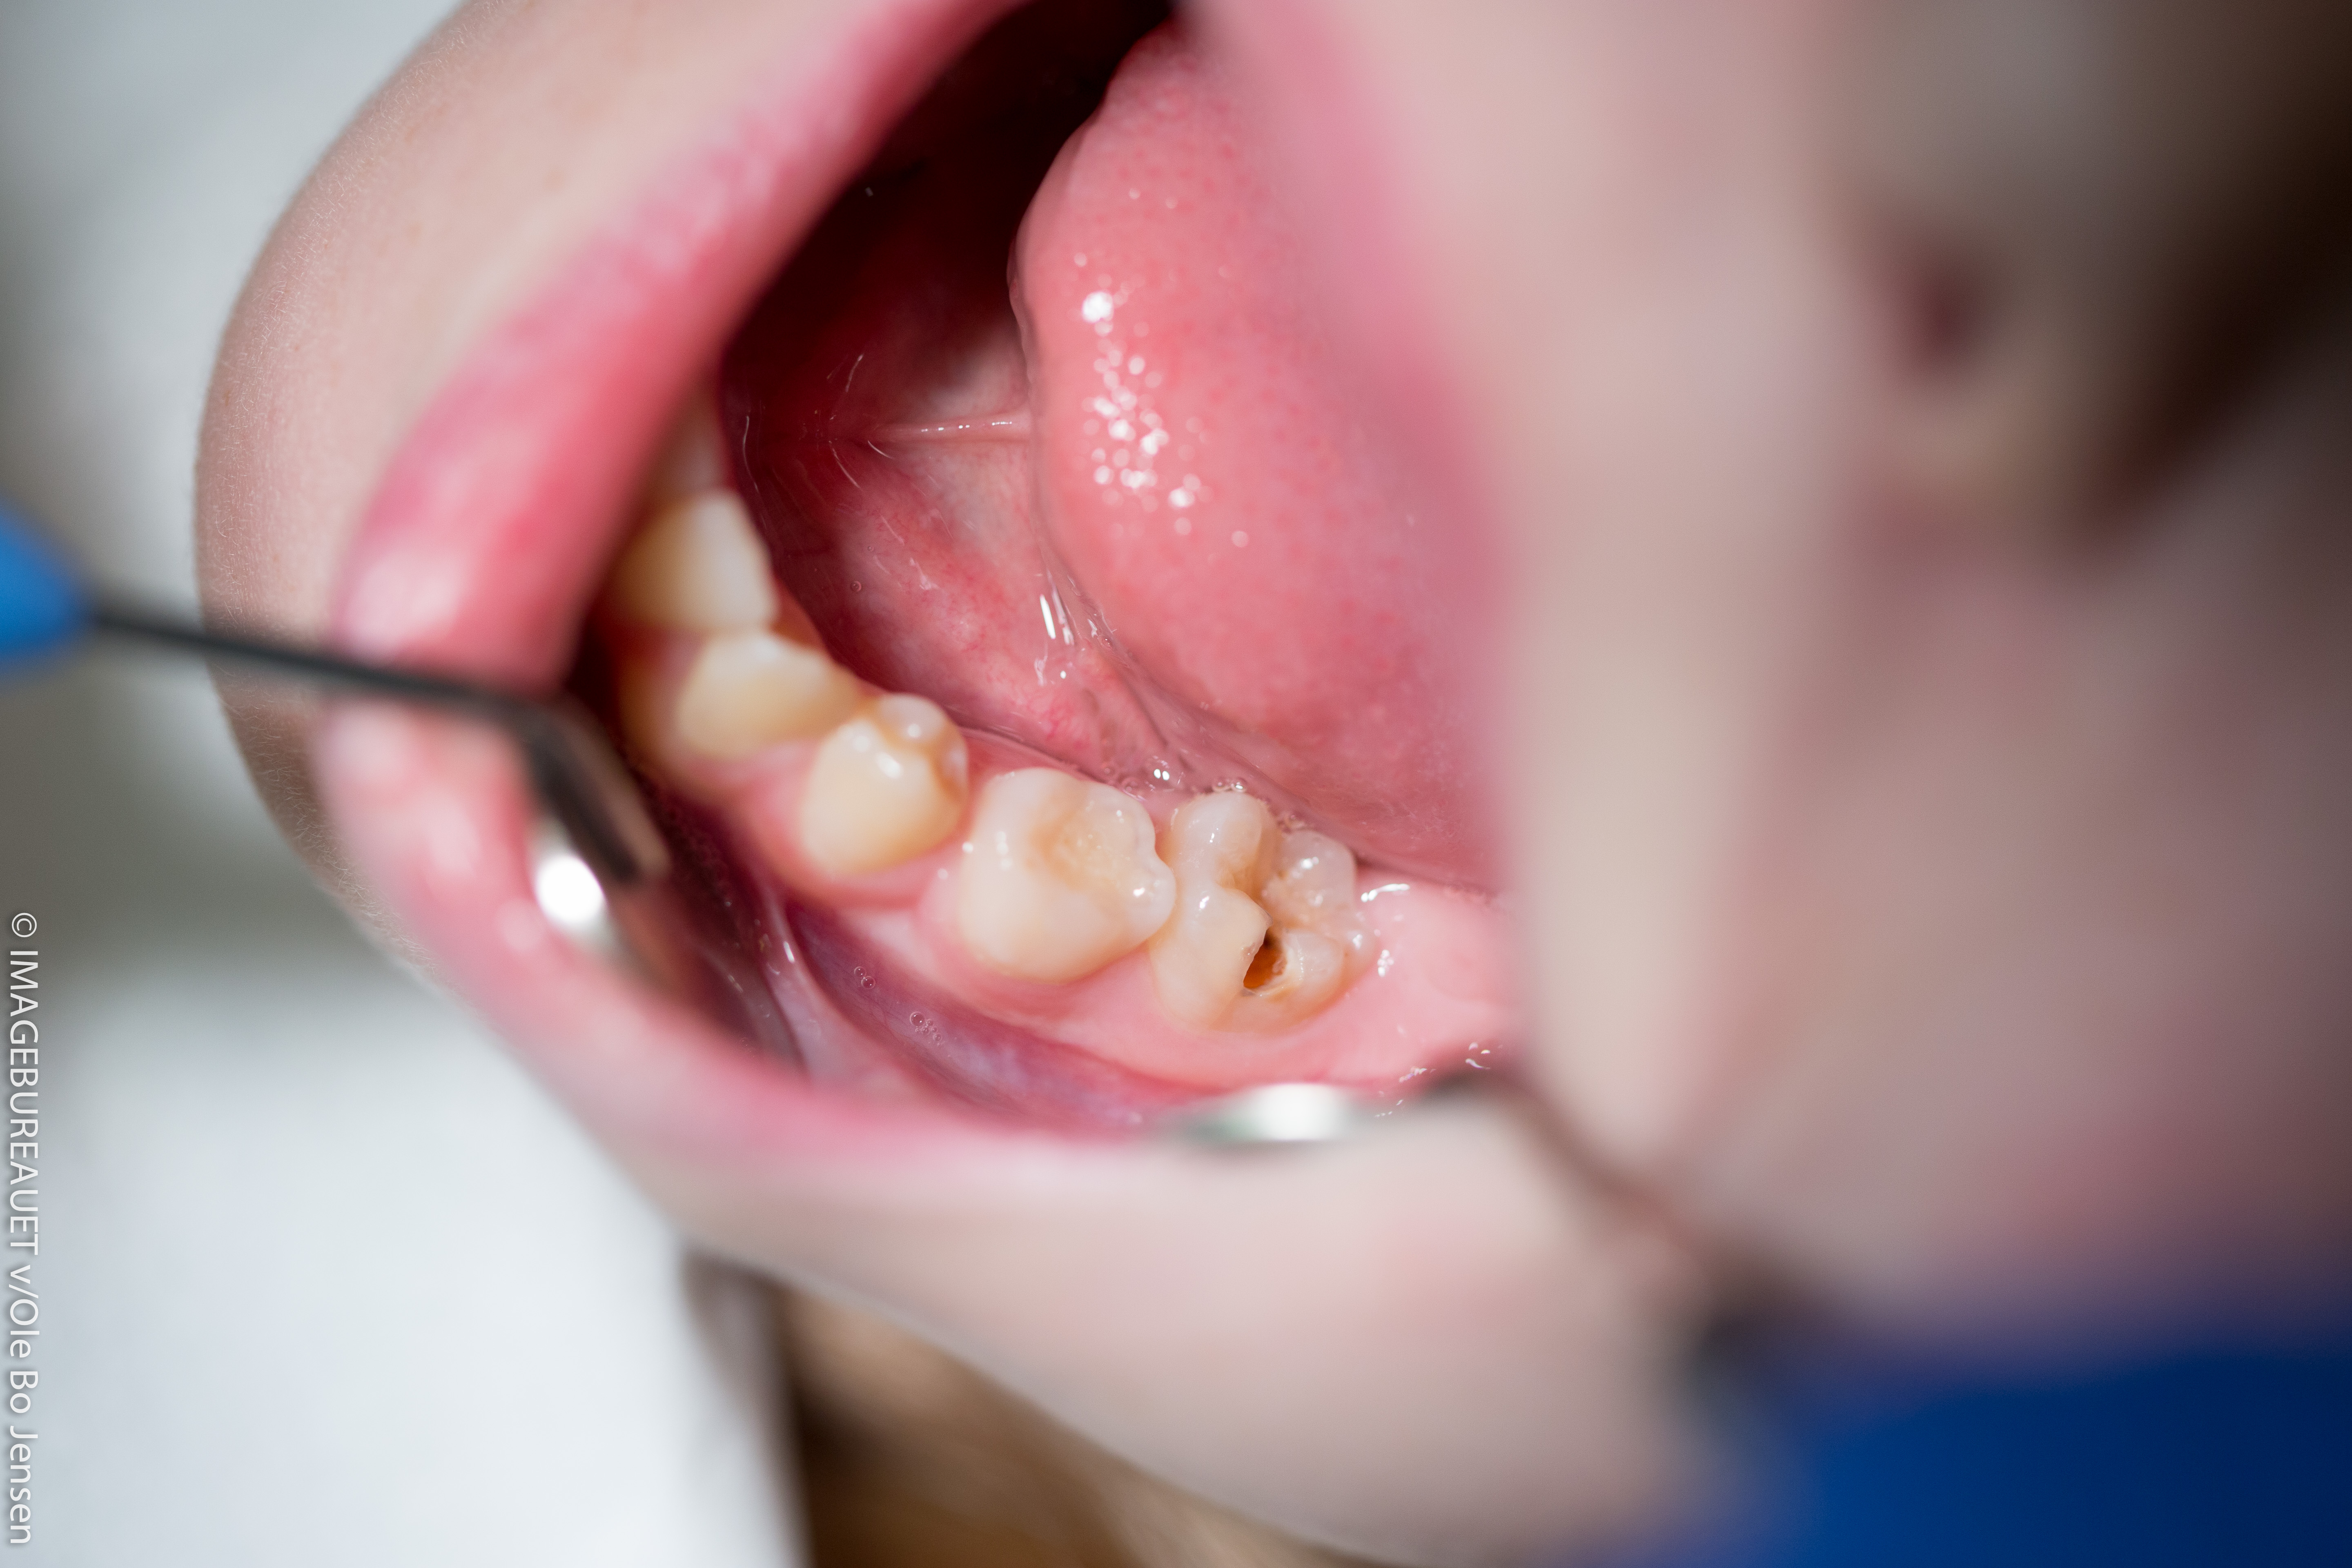

Det er ikke alle huller, som man kan se lige så tydeligt som på billedet her (det brune hul), hvor der er brud på tandens overflade (emaljen). At man kan se hullet, betyder ikke, at det er et stort og dybt hul.

Nogle gange ses huller kun som en svag farveforandring på overfladen. Det er derfor tandlæger bruger så skarpt lys. Det er for at kunne se dine tænder og dit tandkød meget tydeligt. Andre gange tager tandlægen et røntgenbillede for at se, om der er et hul på vej under emaljen eller imellem tænderne. Hvis tandlægen ser, at du er ved at få caries eller tandkødsbetændelse, kan tandlægen hjælpe dig med information og gode råd, så din tandsygdom ikke udvikler sig. Det er derfor en god ide at gå regelmæssigt til tandlæge.